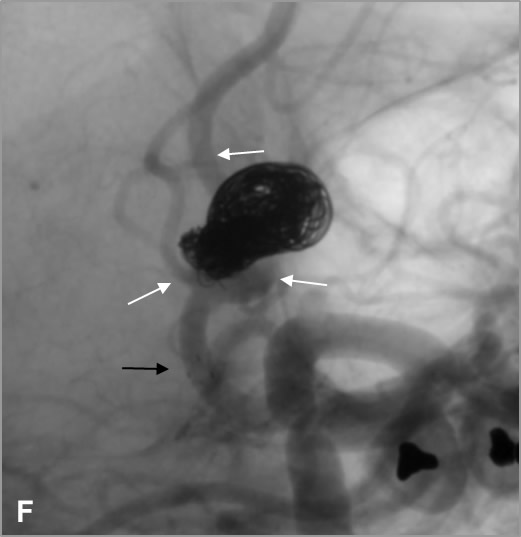

D, E, F: Tratamiento mediante “coiling”, inicialmente simple, posteriormente asistencia con stent mediante técnica “jailing” obteniendo compactación óptima de las espiras (las flechas negras indican las marcas radiopacas proximal y distal del stent; las flechas blancas muestran la permeabilidad de las arterias adyacentes al cuello aneurismático tras el tratamiento).

Ante la necesidad de implantación de stent se comenzó doble antiagregación una semana antes del tratamiento. Se inició el procedimiento mediante “coiling” simple, pero ante el riesgo de comprometer las arterias adyacentes se completó con “coiling” asistido con stent mediante la técnica “jailing”3, dejando el extremo distal del primer microcatéter en el interior del saco aneurismático interponiéndolo entre la malla del stent y la pared arterial. Tras desplegar el stent (Neuroform Atlas®) se completó el tratamiento, consiguiendo una compactación óptima de los “coils”, y evitando la protrusión de espiras que pudieran comprometer las ramas arteriales adyacentes, de especial interés en este caso.